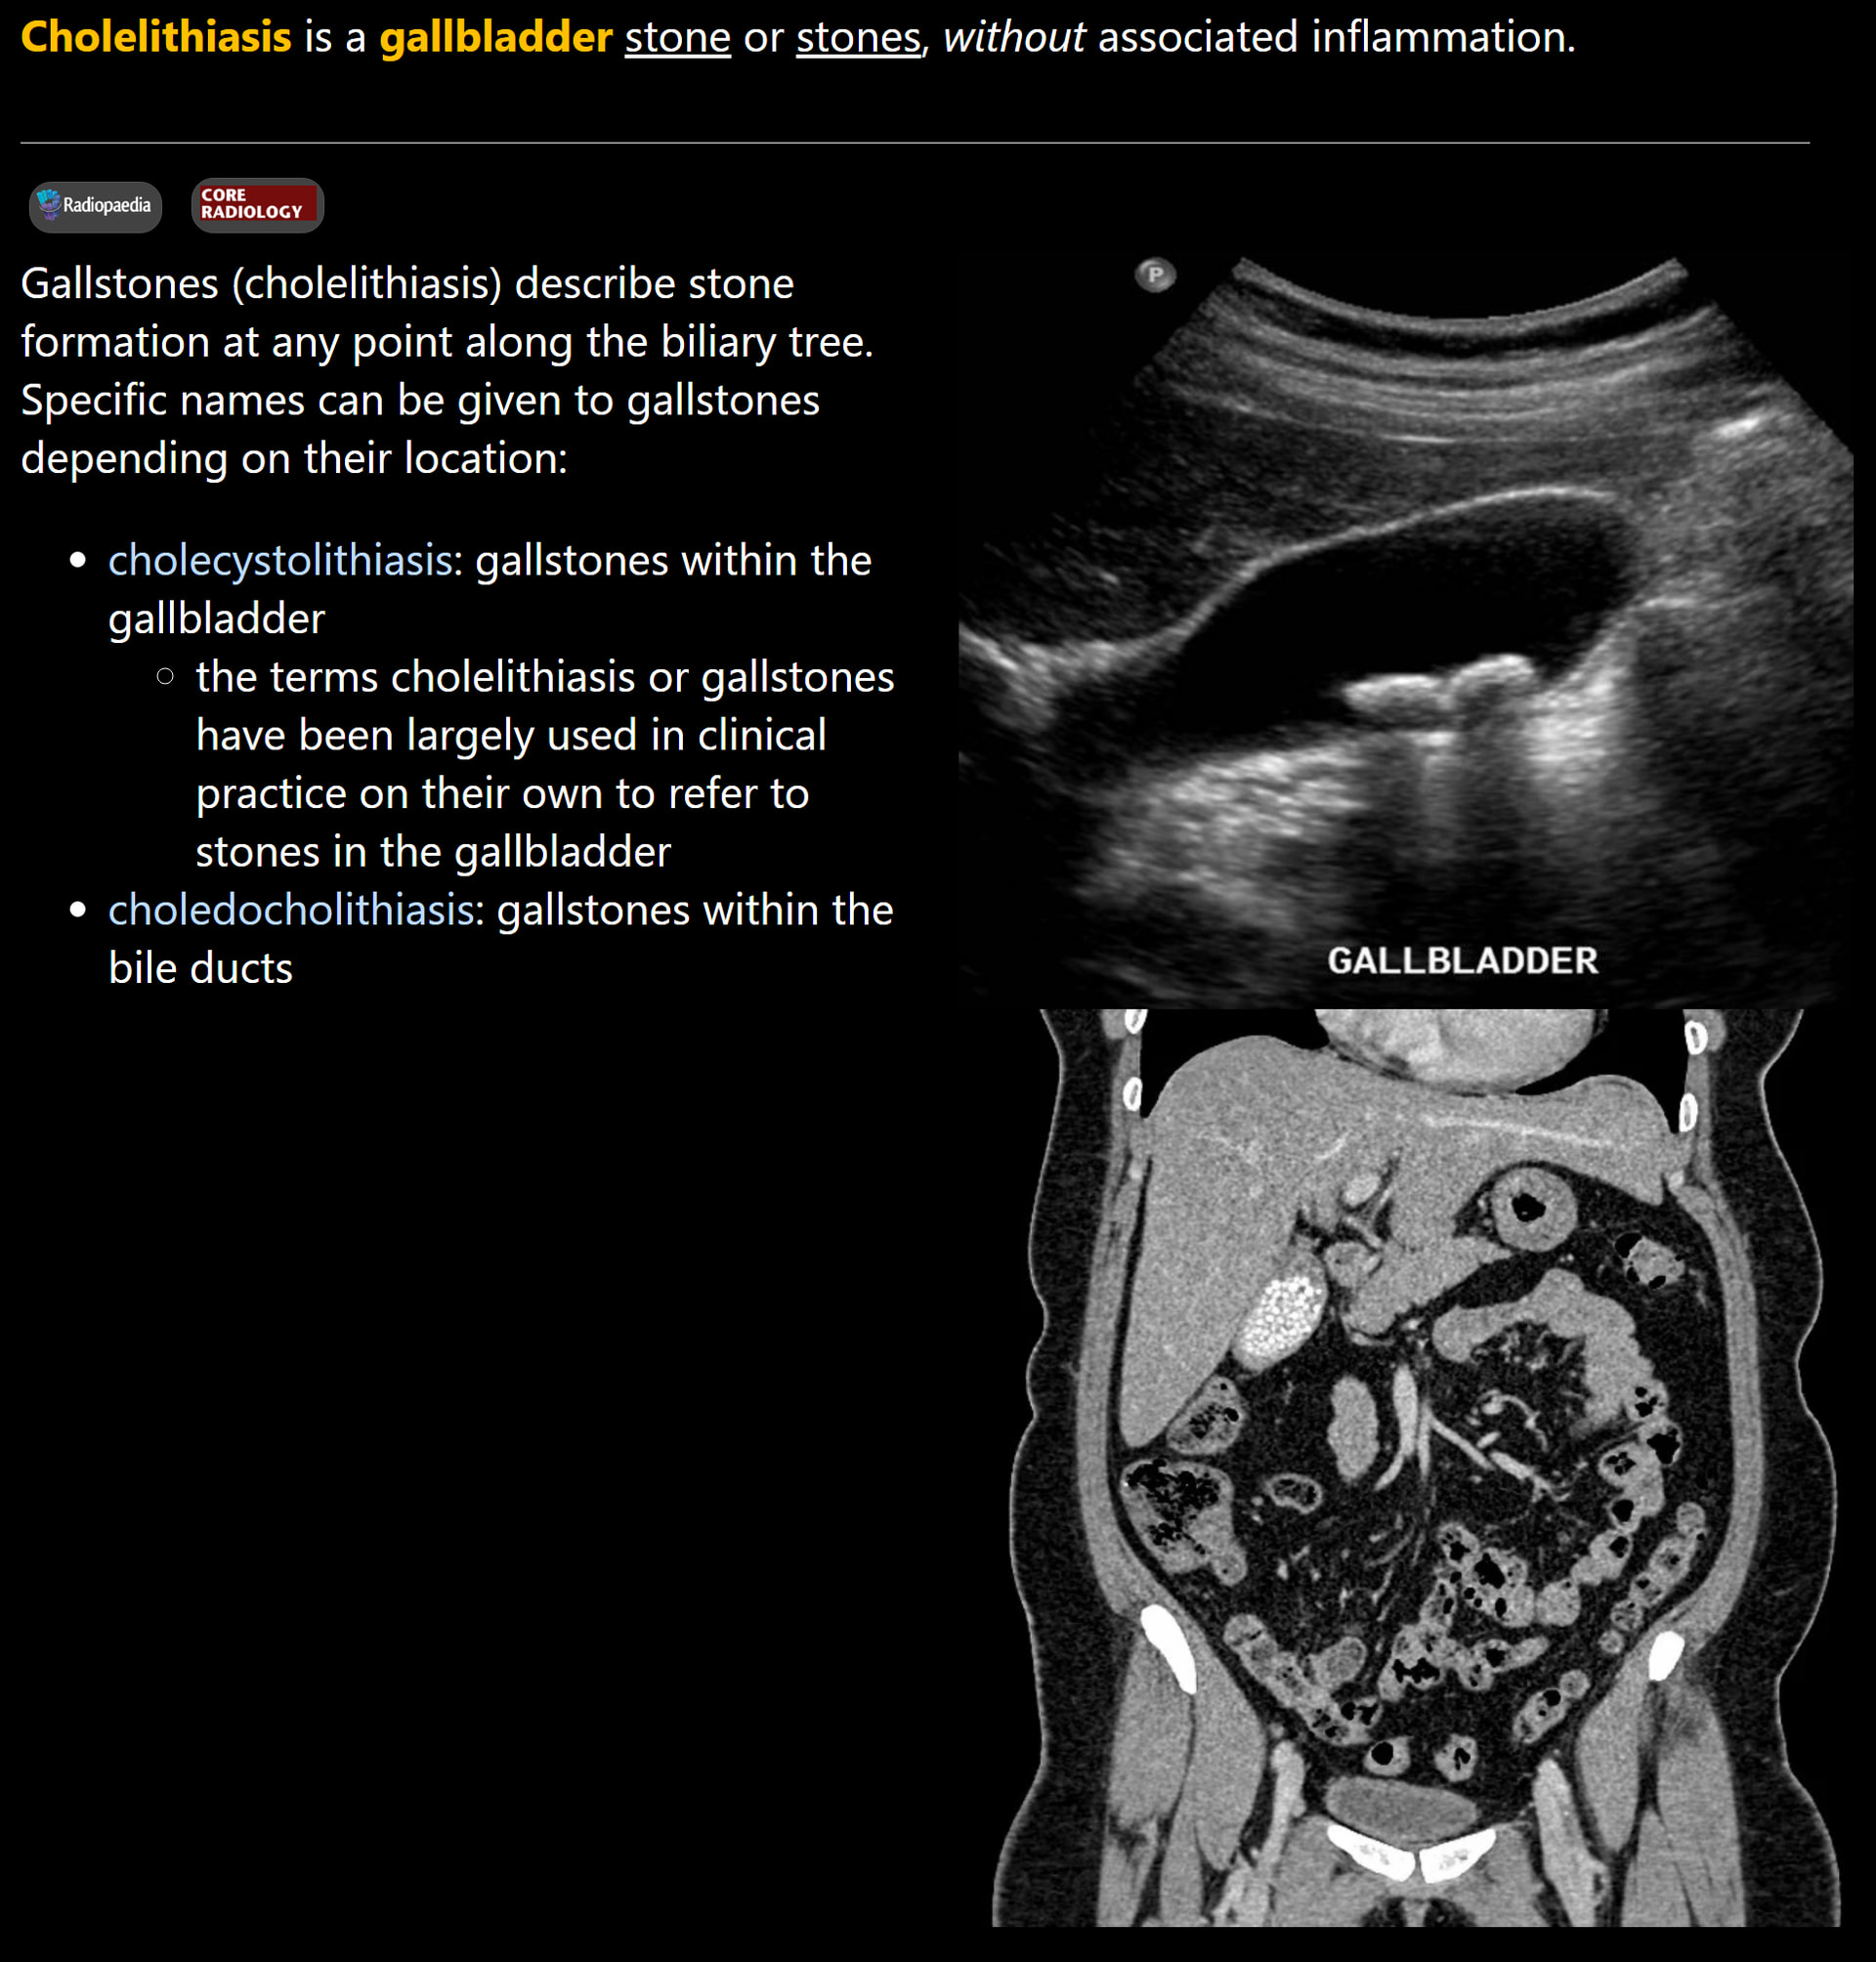

What do the cards look like?

Front:

Back: